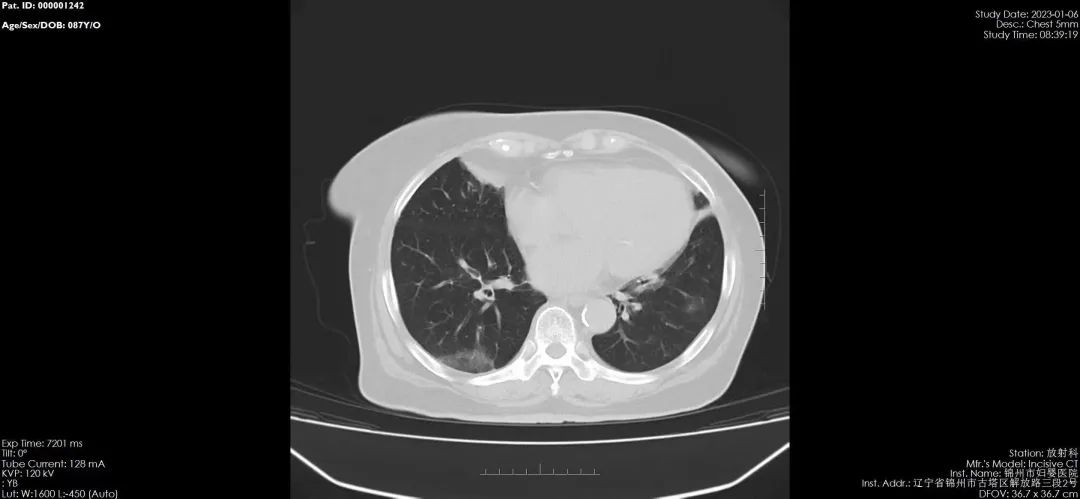

锦州市妇婴医院(妇幼保健院)放射线科,于2020年引进国内最新进口飞利浦64排128层螺旋CT,扫描速度快、分辨率高、层数更薄,对病毒性肺炎有着更高的检出率和准确率,可以更好的与其他肺炎进行区分,对早期肺炎治疗有着非常重要的临床意义。